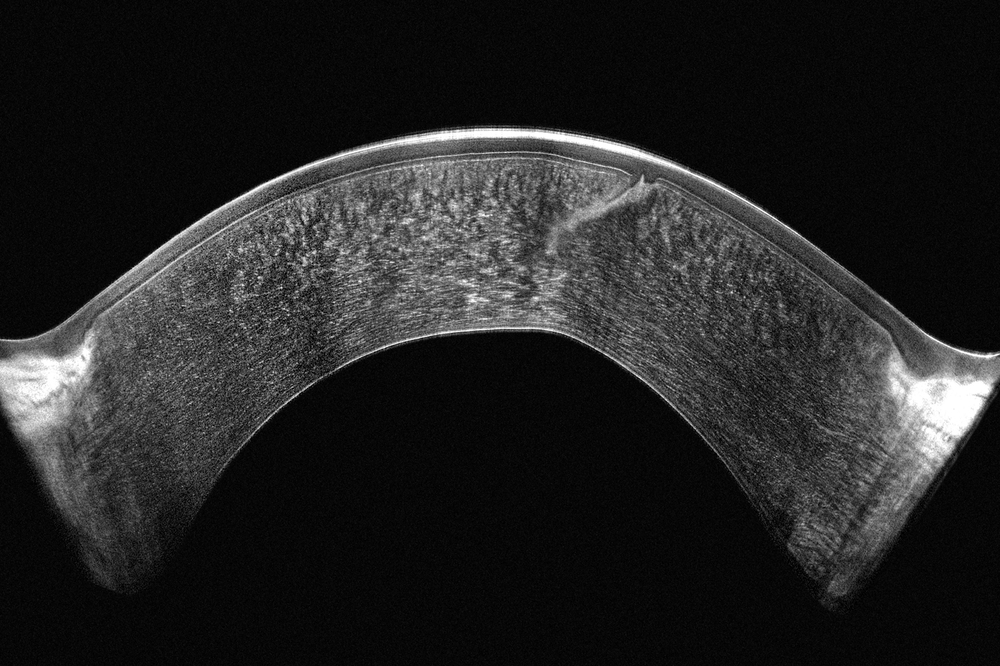

Door Scheimpflug-technologie en OCT te combineren ontstaat een volledig beeld: Scheimpflug toont lichtverstrooiende structuren in het voorste oogsegment met blauw licht, terwijl OCT ongeëvenaarde details geeft. Beide metingen worden gelijktijdig uitgevoerd op exact dezelfde locaties, wat directe en gedetailleerde visualisatie van alle afwijkingen mogelijk maakt.

- Scheimpflug toont verstrooiing;

- OCT geeft gedetailleerde structuren

- Verbeterde nauwkeurigheid: precieze metingen op identieke corneale locaties